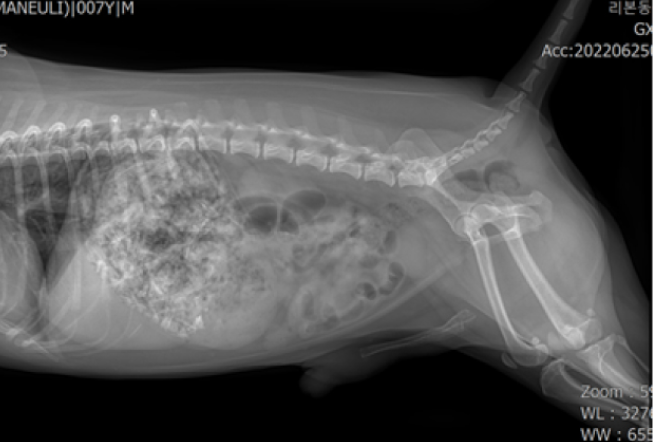

쓰레기통을 뒤져 닭 뼈를 섭취한 7살 치와와 환자가 내원하였으며 X-ray 검사 결과 위장관 내에 날카로운 닭 뼈 부스러기들과 음식물이 정체되어 있는 것을 확인하였습니다.

내원 당시 별다른 임상 증상은 없었으나 x-ray 상에서 위장관 내 닭 뼈 부스러기와 음식물이 다량 보였습니다.

그리고 유문부 쪽에서도 상대적으로 큰 닭 뼈가 관찰되었습니다.

먹은 후 시간이 조금 지난 상태였지만 위장관 내에 계속 저류하고 있는 상황이었습니다.